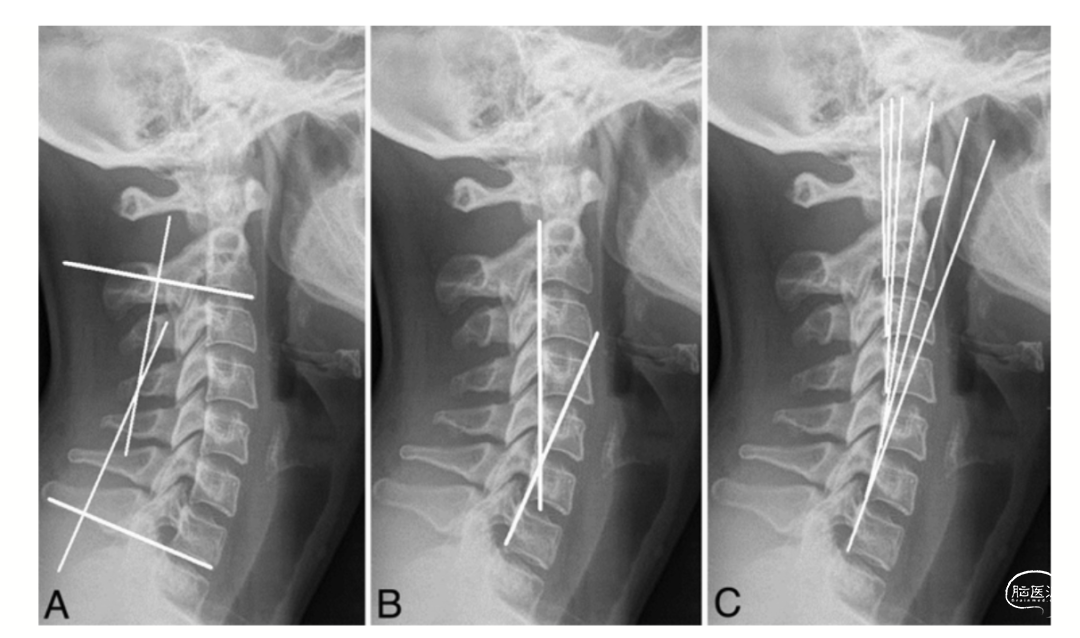

研究者使用Cobb、Jackson和Harrison法在仰卧位MRI和站立位X线片上测量颈椎矢状位序列。根据Cobb角数值对颈椎前凸(> 4°),后凸(<-4°)和正中位(− 4°-4°)进行评估。然后确定了X线片与MRI测量值之间的相关性。同时,研究者评估了观察者自身和观察者之间的测量可靠性。

图5 A Cobb法,B Jackson法,C Harrison法(引自Scheer, J. K. et al. Cervical spine alignment, sagittal deformity, and clinical implications. Journal of Neurosurgery: Spine 2013 19, 2, 141-159)